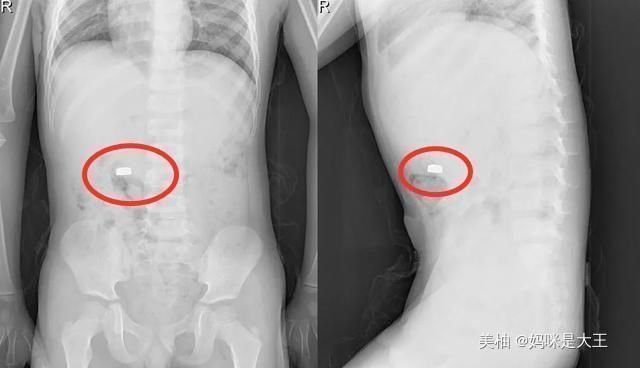

宝妈听到之后一脸惊吓,王女士赶紧来到客厅拿起了孩子的玩具汽车,发现里面的电池确实没有了,然后看到孩子一脸天真的模样,立即带着儿子去了医院。

通过医生的检查,发现孩子的肚子里面确实有一颗纽扣大小的电池,还好王女士立即带孩子来了医院,孩子有惊无险。